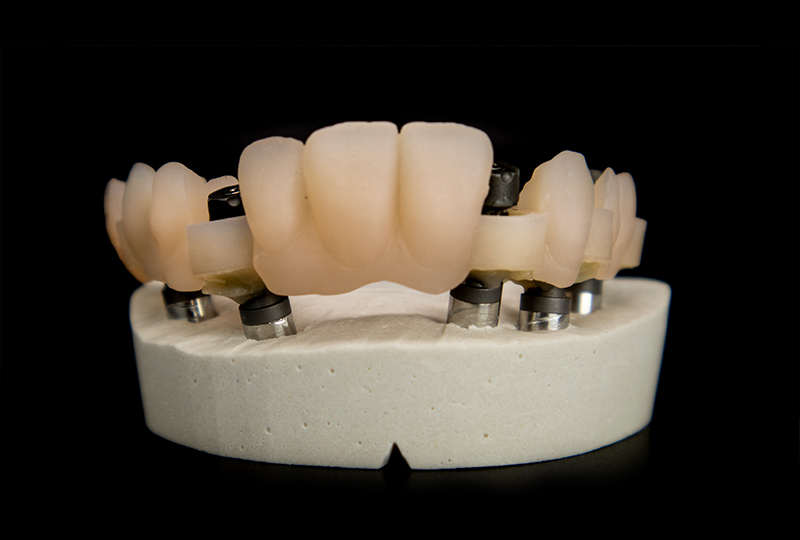

Effettivamente, il provvisorio è molto piacevole. Le resine da stampa 3D e i moderni compositi stanno cambiando il nostro approccio alla produzione dei dispositivi protesici, ma avevamo bisogno di una sottostruttura che garantisse una durata adeguata per la protesi, mirata a sopravvivere oltre i 15-20 anni della vite utile di un impianto dentale.

L’idea per il definitivo era quella di utilizzare una sottostruttura tipo I-Bar fresata in fibra di vetro Zantex, metal-free, e la parte estetica stampata in materiale definitivo certificato, ridotta solo sulla componente rosa, dove un composito a copertura risulta esteticamente più valido. Anche se i materiali scelti non hanno moduli di elasticità comparabili a metalli o zirconia, è necessario avere controlli lungo il flusso di lavoro e un sistema di validazione finale per incollare i tibase nella barra. Contrariamente a quanto si pensa, materiali "morbidi" possono nascondere i problemi, anche all’occhio esperto di un clinico come Diego. Le tensioni, nascoste, scaricano forze incontrollate sugli impianti, portando a problemi di integrazione delle fixture.